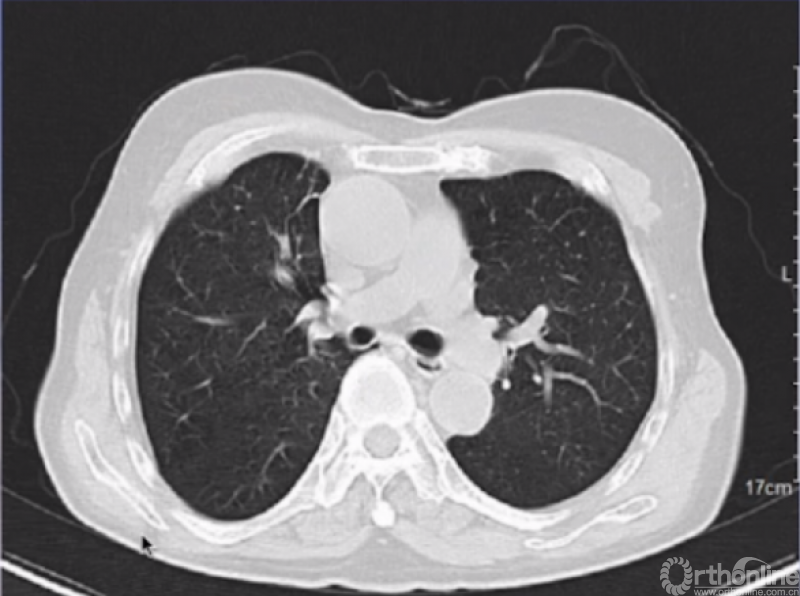

肺部CT

影像所见:平扫肺窗显示两肺纹理增粗、紊乱,支气管壁增厚,小叶中心见多发点状密度增高影;双肺上叶、下叶见散在实性小结节及少许细条索影,边界清;余肺实质未见明显实质性渗出性病变。纵隔窗显示两肺门无增大,气管支气管通畅,血管及脂肪间隙清晰,纵隔未见明显肿大的淋巴结。

影像诊断:双肺慢支、肺气肿改变;双肺散在增殖灶及纤维灶。